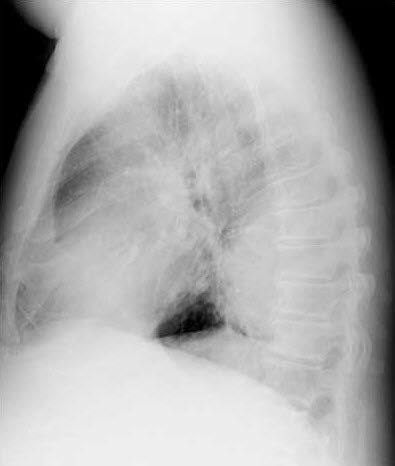

Chest films are ordered.

Chest radiographymay reveal such diagnostic features as:

- LV hypertrophy.

- The classic sign of rib notching, which is caused by erosion of the lower edges of the ribs by dilated intercostal arteries.

- The "reverse 3" sign related to the aortic arch and descending aorta. The upper part of the 3 is formed by the dilated proximal segment descending into the coarctated segment. The bottom portion of the 3 is formed by the coarctated segment as it exits into the normal distal segment of the aorta.